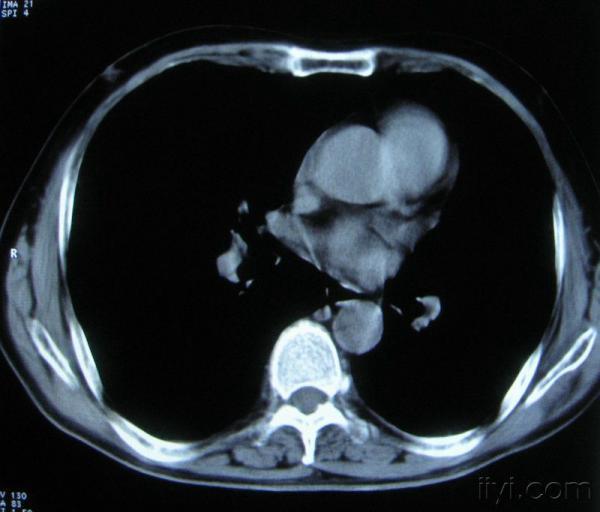

男。60岁,胸片示支气管炎治疗后复查CT。

应该是淋巴结没问题的,中心液化坏死是有这种情况的~~胸科常见到

你指那个肯定是淋巴结,中央系坏死,这很常见,特别在双侧腹股沟会经常看到。这个双侧腋窝及纵隔见多发小淋巴结征。

根据位置考虑应该是淋巴结,密度不均,是因为肿大的淋巴结中心液化坏死